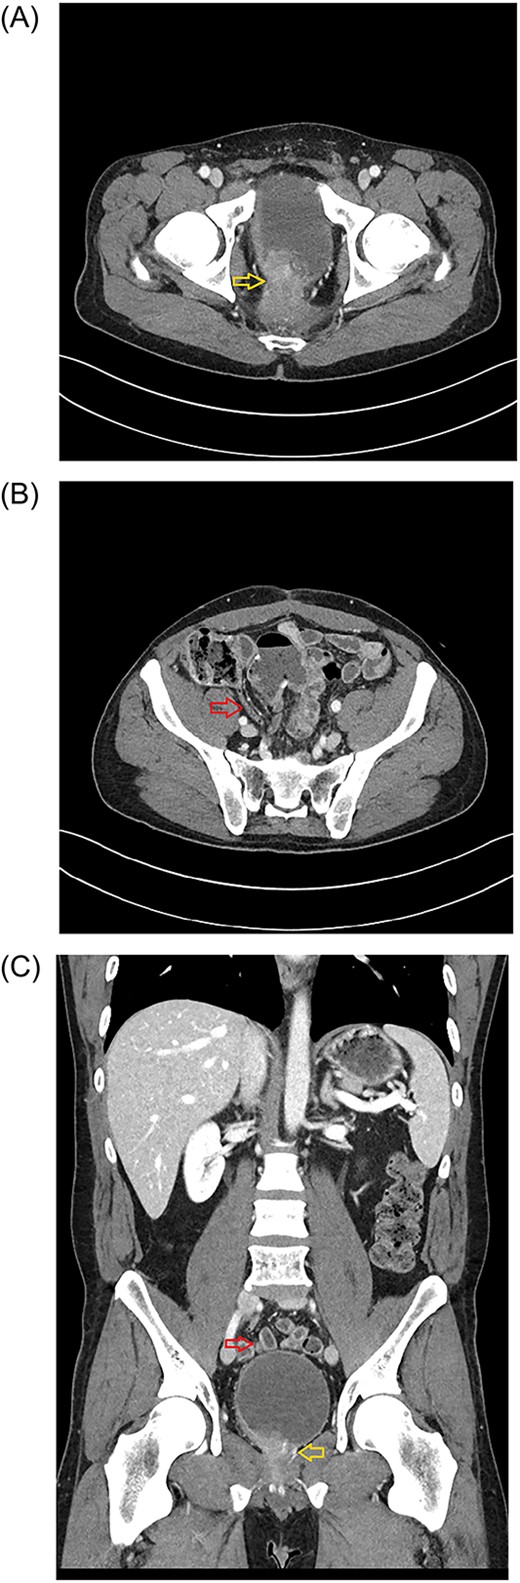

A 38-year-old otherwise healthy male was diagnosed with T3N1 microsatellite-stable rectal cancer after experiencing rectal bleeding, weight loss, and constipation. He completed a two-month course of neoadjuvant chemoradiation, followed by low anterior rectal resection, and three cycles of adjuvant Capecitabine. He declined additional adjuvant chemotherapy due to side effects. Recurrence was found at the colorectal anastomosis 7 months after his initial resection. He underwent abdominoperineal rectal resection with permanent end colostomy. Pathology was moderately differentiated pT2N1M0 microsatellite stable rectal adenocarcinoma. He completed an additional 3-month course of adjuvant chemotherapy before being lost from follow up for almost 2.5 years. He returned to care due to difficulty with urination, numbness, and stabbing pain over the right buttock. Now 4 years out from his initial diagnosis, imaging and biopsy confirmed pelvic recurrence. Imaging showed a presacral soft tissue mass invading prostate and abutting bladder and sacrum, suggestive of perineural spread of the tumor along the right S3 and S4 nerve (Fig. 1A). He completed four cycles of neoadjuvant capecitabine plus oxaliplatin (XELOX) + Panitumumab, followed by neoadjuvant chemoradiation before planned two-stage surgical resection with intraoperative radiation (IORT).

Axial plane of the abdominopelvic CT scan (January 2023) showing the tumor invading bladder (yellow arrow) (A) and the pelvic location of the appendix (red arrow) (B). Abdominal CT scan (Coronal plane) (C) showing the tip of appendix (upper, red arrow) and tumor invading bladder (lower, yellow arrow).

The first stage included a posterior subtotal sacrectomy plus neurectomy of pudendal nerves and neuroplasty of both sciatic nerves. An interval recovery of 24 hours was allowed. The second stage included complete exenteration including bladder and prostate, completion of subtotal sacrectomy, ventral rectus abdominus myocutaneous flap reconstructive surgery to fill the pelvic defect, creation of an ileal conduit and delivery of IORT. During the abdominal portion of the case, prophylactic appendectomy of a benign appearing appendix was done because his anatomy was such that the appendix naturally resided in the pelvis (Fig. 1B and C) and the operative surgeon wanted to avoid need for future appendectomy in a multiply reoperative and irradiated pelvic-exenteration field. His postoperative clinical course was difficult, which was expected for this type of surgery including need for transfusion, urinary tract infection, posterior wound dehiscence, pelvic abscess requiring drainage, and neuropathic leg pain accompanied by foot drop. He has had a slow but steady recovery from the extensive surgery. Unexpectedly, definitive pathology reported appendix with GN at the distal tip (Figs 2 and 3). Given the incidental nature of this finding, preoperative imaging was reviewed. CT scans showed normal appendix without apparent mass (Fig 1B and C).